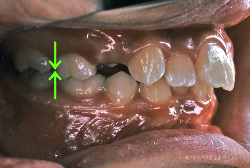

「ものがうまく噛めない」という主訴で来院したケースです。診断の結果、「骨格性反対咬合に伴う咬合不良+軽度叢生」と判明しました。原因としては特に下顎の左側が過成長したため、骨格性反対咬合になり、特に左側での噛み合わせが非常に悪くなっていると診断しました。初診時の写真を見ると、上下の正中線の大きなズレ、左側の噛み合わせの不良がはっきり分かります(黄色の矢印と緑の矢印は一致しているのが正しい状態です)。

そもそも、このような状態となっているのは骨の大きさに問題があるため生じていますので、場合によっては、「外科矯正」によって下顎の骨を外科的に縮めることで修正します。患者様が外科矯正をご希望されない場合は、従来ですと上下左右の小臼歯抜歯を行い矯正するのが普通です。

今回の患者様の場合は、「外科」も「小臼歯抜歯」も拒否されましたので、歯科矯正用アンカースクリュー(以下 アンカースクリュー)を用いて、下顎の歯列全体を後方に下げるという方法を取りました。

治療中の写真で、アンカースクリューより歯を後ろへ牽引しているのがお分かりいただけるかと思います。牽引を1年ほど続け、途中補助的に上下にゴムをかける(これを顎間ゴムと言います)手法なども追加し、全体で21ヶ月で治療を終えることが出来ました。

結局歯の本数を減らすことなく、すべてご自分の歯を残して、正しい配列と噛み合わせにすることができました。凸凹があまりひどくないため、簡単そうに見えると思いますが、このケースの初診の状態を見ると、熟練の矯正歯科医でも悩みのつきないケースです。まして、外科も出来ない、抜歯もイヤ、と言うことになると、従来の方法では治療不可能と考えられるのですが、アンカースクリューを使うことで最近は不可能が可能となってきました。